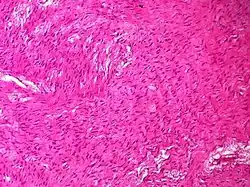

| Sex cord-stromal tumor | Ovarian fibroma | 1.5% | 0% | Spindle-shaped fibroblastic cells and abundant collagen.[11] |

| Adult granulosa cell tumor | 1% | Almost 100% | Small, bland, cuboidal to polygonal cells in various patterns.[12] | .jpg)